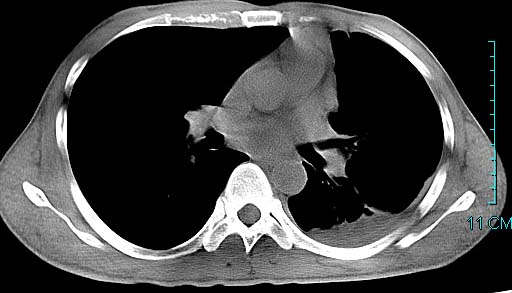

以下是引用ctkz987在2006-3-28 13:04:00的发言:[br]左侧胸腔积液穿刺后多发气液平(多房性),结合临床有高热不除外合并感染。

以下是引用qian在2006-3-28 14:32:00的发言:[br]左肺下叶大片状阴影,密度不均,见有条片影和空洞及气液平,少量胸腔积液伴有胸膜增厚,从图像看积液密度比水的密度高,结合病史,考虑左下肺化脓性炎症伴有脓胸。

以下是引用wawaquan在2006-3-28 22:25:00的发言:[br]左上肺舌段多发斑片影。结合“男24y咳嗽咳痰气促伴高热(38.5--39.5)20多天”及穿刺史,[br]考虑1 左下肺化脓性炎症;2脓胸。

以下是引用乡医在2006-3-28 18:37:00的发言:[br]左侧多发液气平面结合患者男24y咳嗽咳痰气促伴高热(38.5--39.5)20多天,查胸水:ldh239.3,总蛋白59.19,tb-ab阴性,利凡它试验+,红c2.7*109,白c1.08*109,分类淋巴92%分叶8%,考虑1脓胸2肺隔离征感染